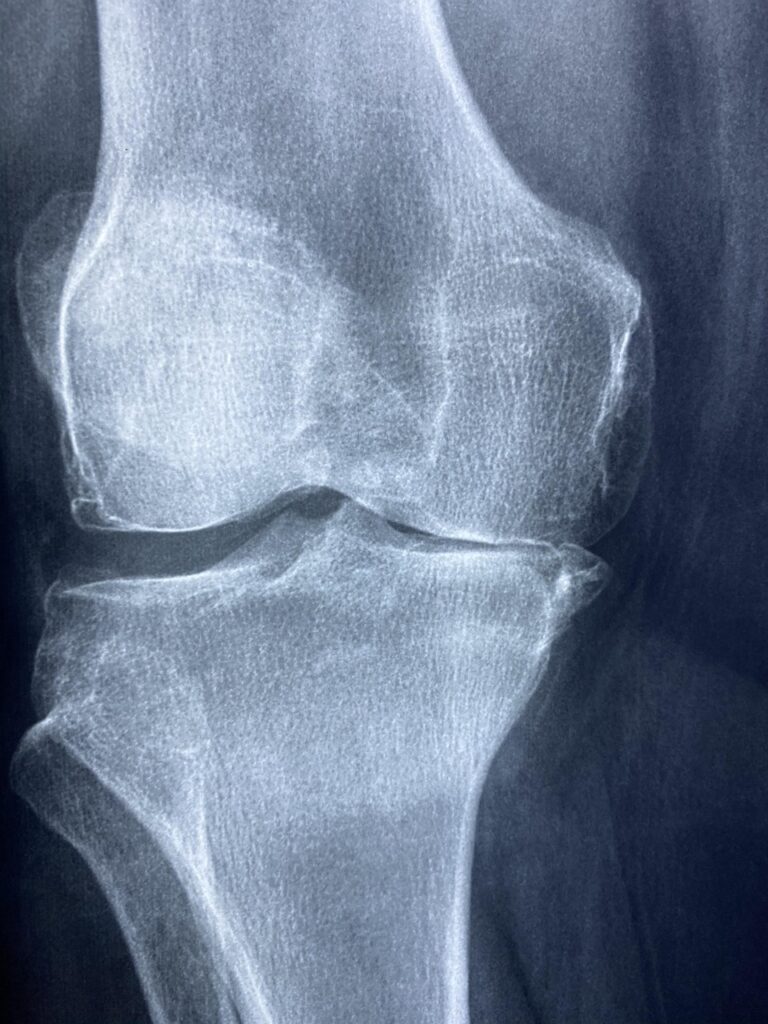

What Causes Knee Osteoarthritis? A Vascular Perspective

For generations, we have been told a very simple story about knee osteoarthritis (OA). It’s “wear and tear.” It’s the inevitable result of aging, running, playing sports, or simply walking on this earth for a few decades. We visualize our knees like the tires on a car—eventually, the tread wears down, the shock absorption fails, […]